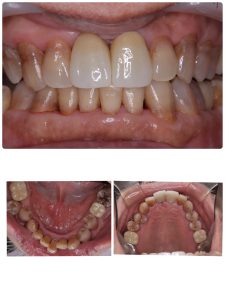

今日で終わり、定期検査に移行の方

インプラント5本、内ソケットリフト2本

今後の観察は、左上下6.7番隣接の骨が如何に増えるか!?動揺はだいぶ減少している💪

EMDにCGFメンブレン使用(再生治療)

後は経過観察